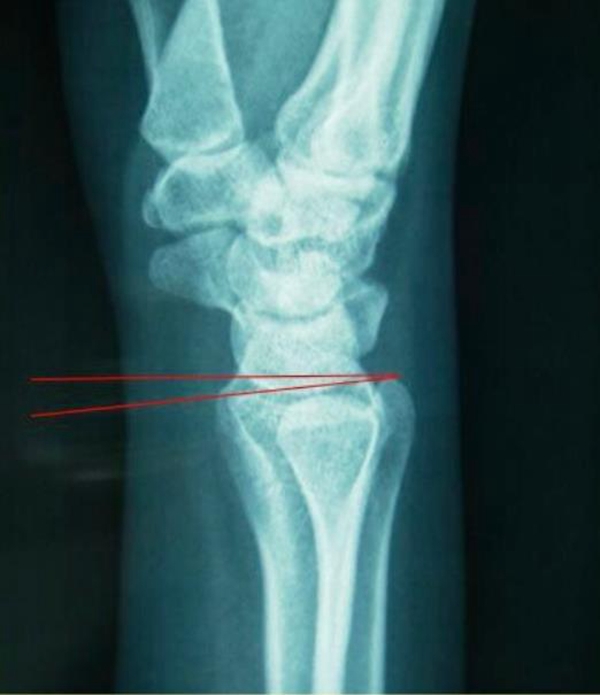

2、桡骨远端正常角度

掌倾10°至15°,尺偏20°至25°。

图2 掌倾角:10°-15°